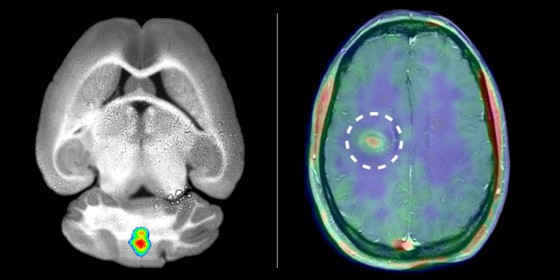

Researchers at the Cells-in-Motion Cluster of Excellence have visualized inflammation in the brain of mice (left) and of multiple sclerosis patients (right). To do so, they labelled specific enzymes (MMPs). - Reprinted with permission from Gerwien and Hermann et al., Sci. Transl. Med. 8, 364ra152 (2016) 9 November 2016

The ultimate aim in biomedical research is the transfer of results from experiments carried out in animals to patients. Researchers at the Cells-in-Motion Cluster of Excellence (CiM) at the University of Münster have succeeded in doing so. For the first time, they have been able to image ongoing inflammation in the brain of patients suffering from multiple sclerosis (MS). This involved specialists from different disciplines working together in a unique way over several years, combining immunology, neurology and imaging technologies ranging from microscopy to whole-body imaging. The consequences of an inflammation in the brain can already be shown using a clinically established process: magnetic resonance imaging (MRI). Making the inflammation itself visible too could, in future, help not only to more accurately diagnose multiple sclerosis patients but also to monitor therapies and apply them in a more specific way. The study has been published in the prestigious journal "Science Translational Medicine".